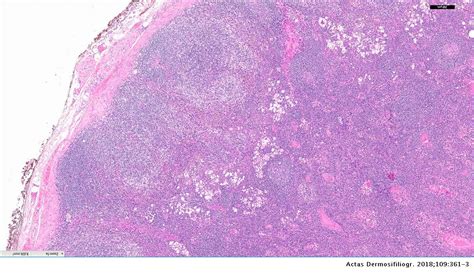

La linfadenopatía dermopática (LD) es una entidad histopatológica caracterizada por el aumento del tamaño de un ganglio, secundario a una dermatosis pruriginosa. Es una forma de hiperplasia paracortical asociada a enfermedades dermatológicas crónicas o, en ocasiones, a entidades sin compromiso cutáneo.

Clínicamente, se manifiesta como un aumento del tamaño de los ganglios linfáticos periféricos, aunque puede observarse en ganglios de tamaño normal. Es importante considerarla en el diagnóstico diferencial de la linfadenopatía periférica, junto con procesos malignos e infecciosos.

La relación entre linfadenopatía palpable y el riesgo de neoplasias sólidas y tumores linfoproliferativos subraya la importancia del diagnóstico y seguimiento de individuos con este hallazgo. Ante un paciente con dermatosis crónica y linfadenopatías, se debe realizar un diagnóstico diferencial que incluya enfermedades autoinmunes e infecciosas, además de las tumorales.

Los hallazgos histopatológicos son característicos: centros germinales ligeramente aumentados, rodeados por linfocitos, y la zona paracortical ensanchada. La zona paracortical aumentada presenta manchas pálidas debido a células de Langerhans y células dendríticas interdigitantes.

Es recomendable el seguimiento estrecho de los pacientes sin diagnóstico clínico objetivo, dado el riesgo de desarrollo de procesos linfoproliferativos, especialmente en la dermatitis atópica. Histológicamente, es preciso diferenciarla del linfoma de Hodgkin o las adenopatías en el contexto de un linfoma T.